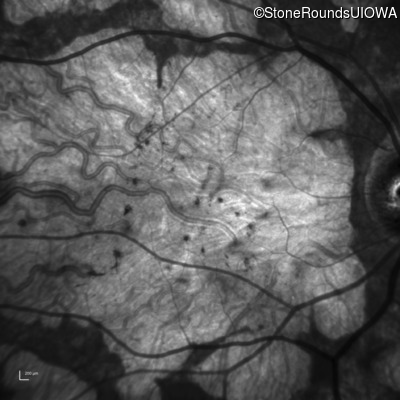

Infrared Fundus Photograph - Right - 20/200 +1 sc

Exemplar

Infrared Fundus Photograph - Left - 20/200 +1 sc